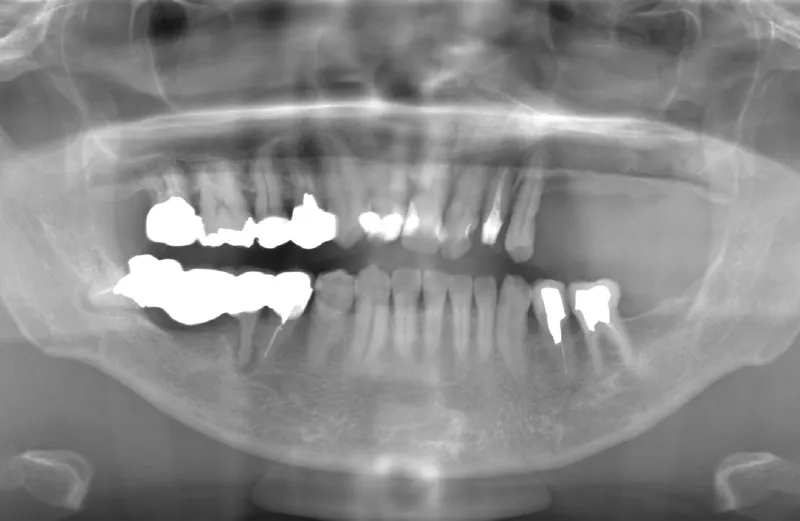

メガジェンオペの症例紹介02

治療前

治療後

| 主訴 | 左上の一番奥歯は他院にてマイクロスコープで治療してもらったが、根の状態が万全ではないのでブリッジでは治療しない方が良いと言われた。 なので左上の歯がないところにインプラントをして欲しい。 |

|---|---|

| 治療期間 | 2ヶ月で仮歯が入り、 3ヶ月で最終補綴物が入って終了。 |

| 費用 | 約550,000円 |

| 治療内容 | エクストラワイドショートインプラントを埋入し、上顎洞を移植材を用いずに挙上しインプラントを埋入した。約2ヶ月で仮歯を装着し、様々な機能面に問題がないことを確認し3ヶ月で最終補綴物を装着して終了した。 |

| 治療のリスク | インプラント埋入オペ時に術者が上顎洞内にインプラントを迷入させる可能性がある。これは術者が技術的に熟練していれば防ぐことが可能。 |